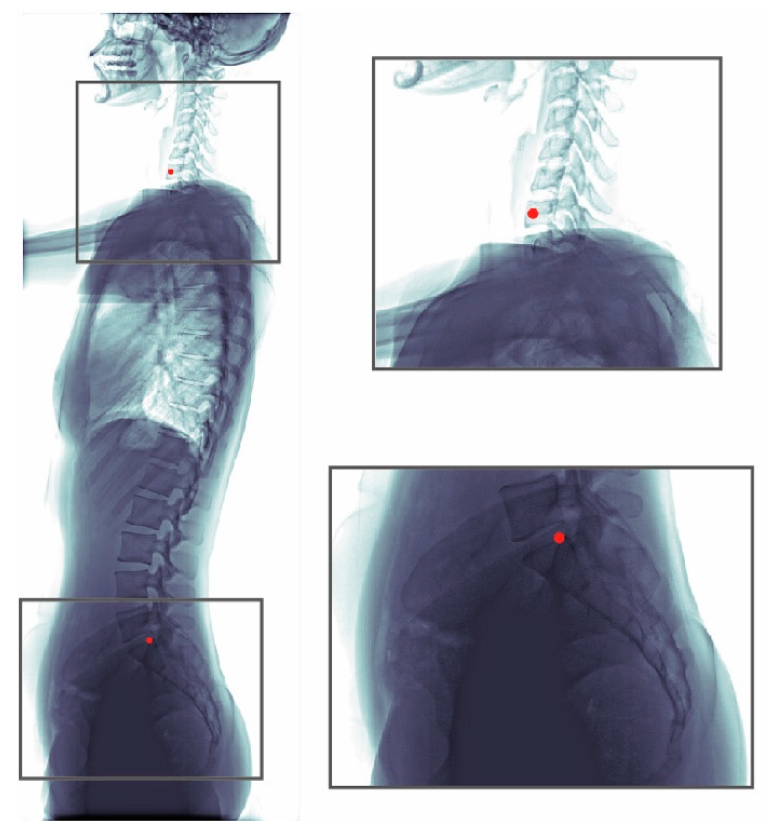

The whole dataset (990 images) was annotated by one senior resident orthopedic surgeon. This surgeon has more than five years of experience for manual measurement of spine parameters. When a difficult case was encountered, the surgeon discussed with an experienced spine surgeon to reach a consensus. This annotated dataset was used for model training and evaluation. An annotated radiograph can be seen in Figure 1. We used a custom written MATLAB GUI program for annotation.

Figure 1. Annotations of a radiograph. The C7 center and the posterior corner of the sacrum were annotated (red dots).